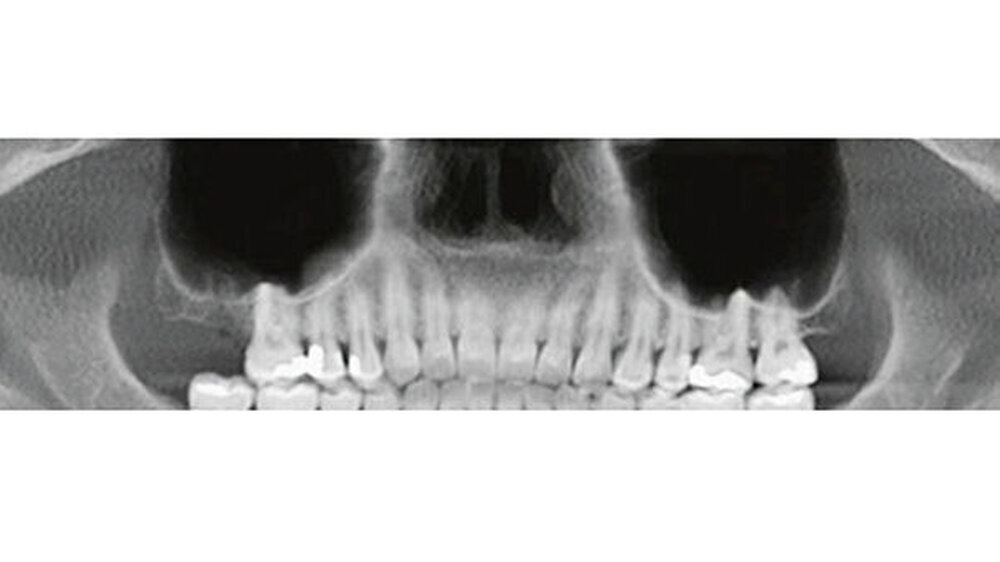

Röntgenologisch (Abb. 1) zeigen sich auf der OPT-Ansicht ein dental und ossär unauffälliger Befund und eine gut belüftete, nicht verschattete rechte Kieferhöhle. Der Verdacht eines Wurzelrests in regio 17 bestätigt sich in dieser Darstellung nicht. Erst nach genauerer Betrachtung der axialen,coronalen und sagittalen Bildebenen des DVT konnte eine zahndichte Verschattung regio Ostium naturale des Sinus maxillaris dargestellt werden, welches kaudal in das Infundibulum ethmoidale und kranial in den Hiatussemilunaris mündet (Abb. 2).